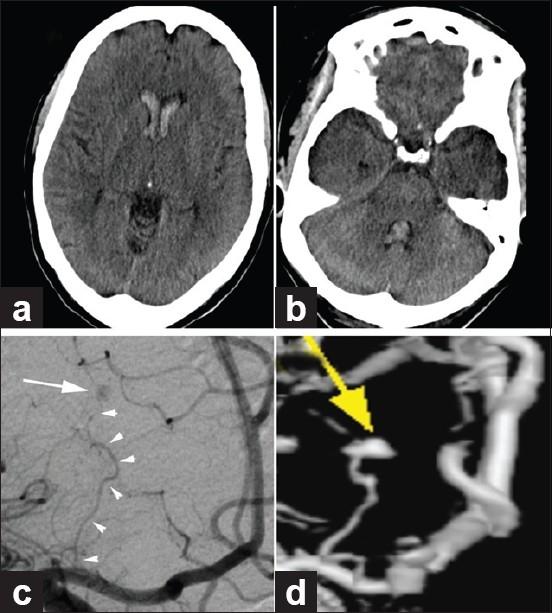

Here we describe a case of isolated or primary IVH (PIVH) in a 71-year-old woman presenting with severe headache. Emergent catheter cerebral angiography, performed after nondiagnostic computed tomography angiography (CTA), revealed the bleeding source to be a 4 × 2.6 mm distal medial lenticulostriate artery aneurysm that ruptured directly into the lateral ventricle. The poorly accessible location of the aneurysm for both endovascular and direct surgical treatment argued for conservative management. A good clinical outcome was obtained with rapid angiographic resolution of the ruptured aneurysm.

在此,我们描述一例71岁女性的孤立性或原发性脑室内出血(PIVH)病例,该患者表现为严重头痛。在非诊断性计算机断层扫描血管造影(CTA)后进行的急诊导管脑血管造影显示,出血源为一个4×2.6毫米的豆纹动脉内侧远端动脉瘤,该动脉瘤直接破裂入侧脑室。该动脉瘤对于血管内治疗和直接手术治疗而言位置不佳,因此主张保守治疗。随着破裂动脉瘤快速血管造影消退,获得了良好的临床结果。